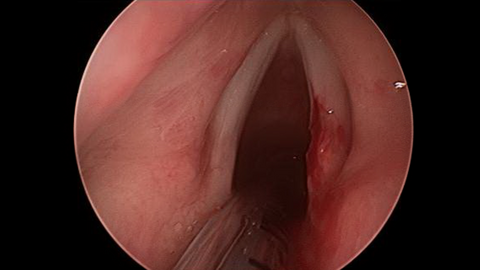

Preoperative Images

Fiberoptic Transnasal Laryngoscopy Showed a smooth yellow lesion on the dorsal surface of the right vocal process; laryngoscopy also showed abundant of lymphoid tissue in the adenoid fossa.